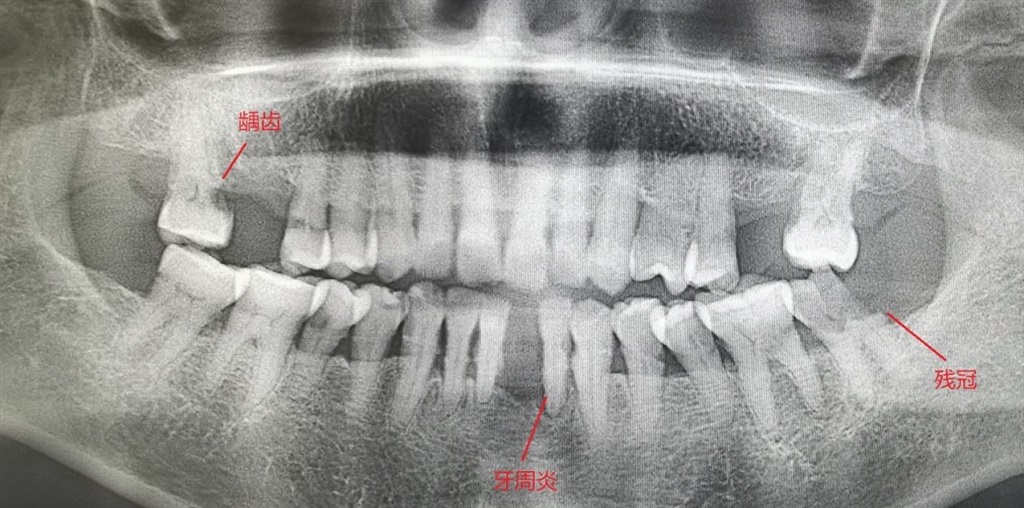

(作者供图 智齿冠周炎)

·智齿冠周炎 是发生在第三磨牙(也称智齿)周围软组织的炎症,多是由于智齿萌出不全或阻生导致。智齿被龈袋覆盖,形成“盲袋”,易导致食物残渣残留,若清理不干净,可引起细菌滋生,引发急、慢性炎症。智齿冠周炎多发生在18~30岁的人群,这个年龄段恰好是多数女性选择怀孕的时间,因此智齿冠周炎在妊娠期妇女中很常见,症状多表现为智齿周围牙龈肿胀、疼痛,严重者可表现为张口受限,进食吞咽困难,面部肿胀,甚至体温升高、食欲减退、头痛等全身症状,进而对孕妇和胎儿造成一定的影响。因此,孕前一定要进行智齿检查,有可能引起发炎的智齿应在怀孕前尽早拔除。

Part2 孕前口腔检查有哪些内容? ·牙龈炎和牙周炎 孕前口腔检查也称孕前口腔体检,其中很重要的一项内容为:检查患者口内是否有牙结石(包括牙龈上结石和牙龈下结石),有无牙龈红肿、出血,有无牙龈增生,有无牙根暴露、牙齿松动。治疗建议一般为:全口洁治(即洗牙);有牙龈下结石的还需龈下刮治;牙龈已有增生且无法用保守治疗消除的,必要时需行手术治疗;牙齿松动严重无法保留的需尽早拔除。 注意:严重的牙龈炎和牙周炎,治疗期间需配合使用抗生素。 ·龋病、非龋性疾病、牙髓炎和根尖周炎 孕前口腔检查第二项重要的内容为:检查患者是否有龋齿、非龋性疾病(包括楔状缺损、牙磨损、牙隐裂等),是否已发展成牙髓炎或根尖周炎。治疗建议一般为:充填治疗;严重的患牙需进行根管治疗进行试保留,即俗话说的“烂牙神经”,根管治疗疗程一般为3~5次,间隔1周左右;对于无法保留的残冠残根应尽早予以拔除。 注意:诊断及根管治疗过程中可能需要拍摄口腔X线片,严重的炎症需配合使用抗生素,因此建议孕前3~6个月进行口腔牙齿检查。 ·智齿 孕前口腔检查第三项重要的内容为:检查患者口腔内是否有智齿,方向如何,是否被牙龈覆盖,是否与前牙有食物嵌塞,是否伸长,是否为废用的牙齿。治疗建议为:拔除有症状或潜在风险的智齿。 注意:智齿的诊断及治疗过程中有可能拍摄口腔X线片和口腔CBCT片,智齿拔除后需使用抗生素减轻感染,因此建议孕前3~6个月进行口腔智齿检查。 此外,孕前口腔检查的内容还包括检查患者口内是否有缺牙,若影响进食则建议孕前修复缺失牙;是否有不良修复体,若易引起牙龈炎症牙齿疼痛,则建议拆除不良修复体。 Part3 孕期如何进行口腔维护? 1、饮食调整 牙发育是一个长期、复杂的过程,乳牙从胚胎第2个月开始发生,恒牙在胚胎第4~5个月开始发生。怀孕期间尽量控制酸甜食物的摄入,保证营养摄入均衡,怀孕早、中期需多摄入富含蛋白质、钙、磷和维生素D的食物,这对胎儿的骨骼和牙齿发育至关重要。 2、口腔清洁 妊娠期的母体处于一种特殊状态,激素水平改变、摄食次数与食量增多,生活规律改变等,使口腔卫生变差。因此需加强口腔清洁,做到饭后刷牙,使用软毛牙刷竖向刷牙,每次刷3分钟,除牙刷外,需配合使用辅助工具,如牙线,牙缝刷和冲牙器进行牙缝和牙龈沟的清洁,做到有效清洁,预防妊娠期龈炎的发生。